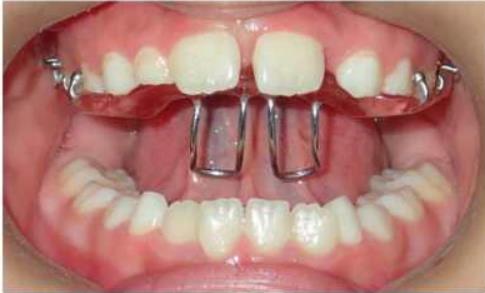

② 前方牵引矫治器

矫治方法:后牙反合的患儿往往因为有龋齿而形成偏侧咀嚼的习惯,应及时治疗后牙区龋齿,纠正其偏侧咀嚼的习惯。乳牙列和混合牙列期的主要治疗方法主要通过调合以及扩展上牙弓宽度。常用的矫治器为Haas扩弓器和Hyrax扩弓器。

Haas扩弓器

Hyrax扩弓器